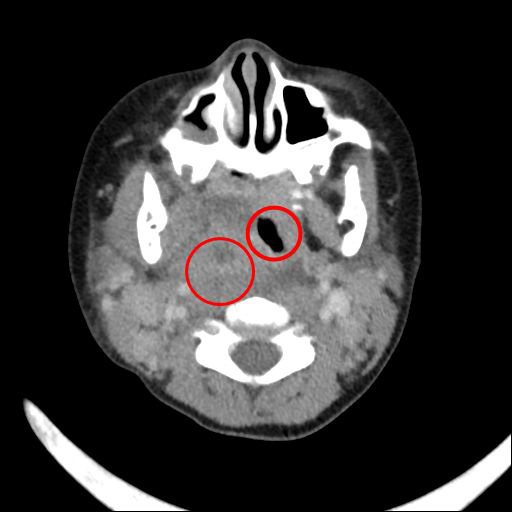

【發燒脖子腫要當心,深頸膿瘍恐致命】

2021-03-03

兩歲半的小涵(化名)因持續兩三日的發燒,且不願開口說話、進食,被送往花蓮慈濟醫院就診,檢查發現是深頸部後咽腔膿瘍壓迫所致,經小兒部張雲傑醫師診斷需盡快動手術,並立刻聯繫耳鼻喉科周昱甫醫師做清創和引流,所幸小涵在術後恢... <詳全文>